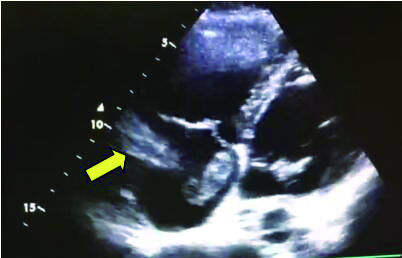

例4 62岁,女性,主诉“活动后气短20 d,加重1 d伴晕厥1次”。患者入院20 d前上近20级台阶后感气促,休息后缓解,未重视。入院前1 d,突发晕厥伴有轻微活动后明显的呼吸困难。既往:左下肢静脉曲张病史3~4年;入院40 d前患者左足跖骨骨折,接受外固定,尚未影响日常活动,未接受抗凝治疗;发现血小板减少数年(血小板维持5.5~8.6 g/L,末次于一年前血小板85 G/L),未明确原因及治疗;血气分析提示pH 7.447,PaCO2 32.2 mmHg,PaO2 85.3 mmHg,SaO2 96.8%;D-Dimer 1 947 ng/mL;FDP 22.84 μg/mL,FBG 2.05 g/L;PLT 51G/L;cTnI 0.52 ng/mL,BNP 299 pg/mL;ALT 318 U/L,AST 300 U/L,CREA 74.8 μmol/L,血Na+、K+、Cl-:正常范围;UCG提示:右心大,肺动脉主干轻度增宽(28 mm),三尖瓣反流(重度),反流面积13.7 cm2,TI法估计SPAP为30 mmHg、左室舒末内径35 mm、左室舒张功能受限(E/A 1:1.5)、未见节段性室壁运动障碍;双下肢静脉超声提示左侧腘静脉不完全血栓。心电图(图 12所示)提示窦性心动过速、SⅠQⅢTⅢ;CTPA显示肺动脉分叉处及双肺亚段充盈缺损(图 13所示)。

| 图 13 入院时CTPA结果显示肺动脉分叉处及双肺亚段充盈缺损 |

入院查体:神志清楚,体温36.5℃,血压120/70 mmHg,脉率110次/min,呼吸22~26次/min,指氧饱和度93%(安静,空气氧),未见乏氧征。双肺呼吸音清,未闻及干湿性啰音,心率110次/min,律齐,P2 > A2,心界无扩大,无杂音,腹软,无压痛,肠鸣音正常。神经系统未见异常。左下肢膝关节以下可见静脉曲张,双下肢无浮肿。入院诊断:急性肺血栓栓塞症(中高危);左下肢静脉曲张并血栓形成;血小板减少症;肝功能不全。处理方法及原因:患者中年,日常生活质量高;入院20 d前虽有症状,但入院1 d前明显加重并出现晕厥发作;两次D-Dimer检查均<2 000 ng/mL,与CTPA显示的血栓负荷不匹配。入院后连续两次检测血小板均低于正常(51~77 g/L)。因考虑病史较长但近期有加重、血小板低等原因系统溶栓治疗出血风险较大,所以给予导管介入碎栓并行肺动脉内溶栓治疗(r-tPA 20 mg)。溶栓2 h后患者症状明显缓解,复查D-Dimer 12 560 ng/mL,序贯肝素抗凝并复查CTPA提示原有血栓明显消失(图 14所示)。

| 图 14 介入溶栓后患者CTPA结果提示明显改善 |

患者特点及再灌注治疗时机及方式选择:患者病程20 d,但是入院前1 d呼吸困难加重同时伴有晕厥,提示1 d内有明确的新的血栓脱落导致的一过性脑缺血。理论上讲,如果纤溶功能正常的话,CTPA显示的血栓负荷与D-Dimer具有一定的匹配性,而本例患者连续两次检测并未发现这种匹配的特点,分析原因有两种可能:①原有主肺动脉干血栓负荷较大,近期虽然有新的血栓脱落,但新鲜血栓的负荷量不足以大到D-Dimer明显升高的地步;②主干血栓为近期一次脱落而成,但是患者有存在继发纤溶低下的可能,同样表现为较低的D-Dimer水平。如果存在继发纤溶功能低下的话,难以避免单纯抗凝治疗后栓塞性肺动脉高压的风险。我们决定给予介入下的碎栓并肺动脉内溶栓治疗是考虑原有血栓阻塞左右肺动脉主干,很难代偿新鲜血栓的再次脱落。更重要的是,CTPA提示肺动脉主干的骑跨血栓密度尚不支持陈旧血栓。溶栓后CTPA结果也验证了对CTPA结果解读的正确。本例患者另一个特点D-Dimer水平与血栓负荷不成比例的另一个依据是凝血机制检测提示纤溶系统异常,PAI-1活性超过正常3倍,证实了最初的判断。